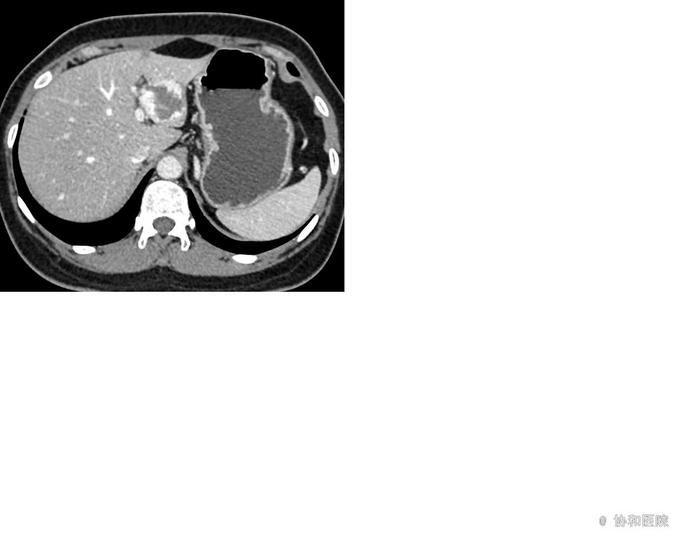

女,46岁, 主诉:体检发现肝占位性病变10年 现病史:患者于2005年6月8日在秦皇岛市第一医院体检,自述行腹部超声示:肝内低回声,考虑血管瘤可能,大小约为3.5×2.2cm(未见报告)。患者无腹痛、腹胀,无纳差、黄疸,无恶心、呕吐等不适,未予特殊治疗。2013年10月10日在当地医院复查腹部超声示:肝内低回声,大小约为3.6×2.6cm。近2年来,患者多次行腹部超声、CT及肝脏造影检查,均提示肝占位性病变,考虑肝血管瘤,逐渐增大。2015年7月7日再次于秦皇岛市第一医院体检,行腹部超声示:肝内低回声,考虑血管瘤可能,大小约为5.3×3.2cm。现患者为进一步明确诊断,积极、合理治疗,来我院门诊就诊,以“肝占位性病变”收治入院。

腹部超声(2015-7-7,秦皇岛市第一医院):1、肝左叶低回声,考虑血管瘤,大小5.×3.2cm。2、脂肪肝。3、肝囊肿。

肝血管瘤 手术切除